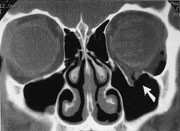

Drusepapiller er den hyppigste årsak til pseudopapillødem, og det fundoskopiske bildet kan lett forveksles med papillødem. Orbital CT kan påvise små forkalkede hyalinlegemer ved papillen (fig 3).

CT med koronalt og aksialt snitt er å foretrekke ved endokrin oftalmopati. Et karakteristisk CT-funn er en relativt symmetrisk forstørrelse, først og fremst av nedre og mediale rette øyemuskler. I 90 % av tilfellene kan det avdekkes patologiske forhold bilateralt, til tross for ensidige symptomer. Aksiale og koronale plan viser godt fordelingen og graden av muskelforstørrelse og forholdet til synsnerven ved orbital apex (8). Det er en relativ sparing av muskelsenen, mens det er særlig fortykket midtre og bakre del ved muskelbunten som er typisk og muliggjør differensiering fra myositt. Endokrin oftalmopati forekommer i 2 – 7 % av tilfellene av Graves sykdom, i aktiv fase med inflammasjon og lymfocyttinfiltrasjon i retrobulbært orbitalt vev, i utbrenningsfasen med fibroser. Et fokalt lavattenuerende område innenfor muskelbunten er et annet CT-funn som tyder på endokrin oftalmopati. Tidlig i forløpet finnes lymfocytisk infiltrasjon og fokal mukopolysakkaridavleiring, mens fettinfiltrasjon forekommer i den senere fasen. Andre hyppige funn ved Graves sykdom er ekspansjon av det orbitale fett, som presser orbitalseptum fremover og dermed strekker synsnerven.

Idiopatisk inflammasjon eller pseudotumor intraorbitalt opptrer ofte som uni- eller bilateral rød smertefull protrusjon av øyet med innskrenket bevegelighet. Dette er den tredje hyppigste tilstanden etter endokrin oftalmopati og lymfoproliferative sykdommer. De fleste inndeler tilstanden ut fra av lokalisasjonen. 95 % av tilfellene viser kontrastoppladning på CT, 76 % retrobulbær fettinfiltrasjon, 71 % proptosis og 57 % asymmetrisk fortykkede muskler (10). I slike tilfeller er både muskelbunten og senen fortykket, og hyppigst affisert er de mediale og øvre rette øyemuskler. I motsetning til ved Graves sykdom er det orbitale fettinnholdet ikke økt. Hvis inflammasjonen er nær bulbus, sees kontrastoppladning i sclera. CT er like nyttig ved denne tilstanden som MR, og er en billigere undersøkelse som tar kortere tid, men gir strålebelastning.